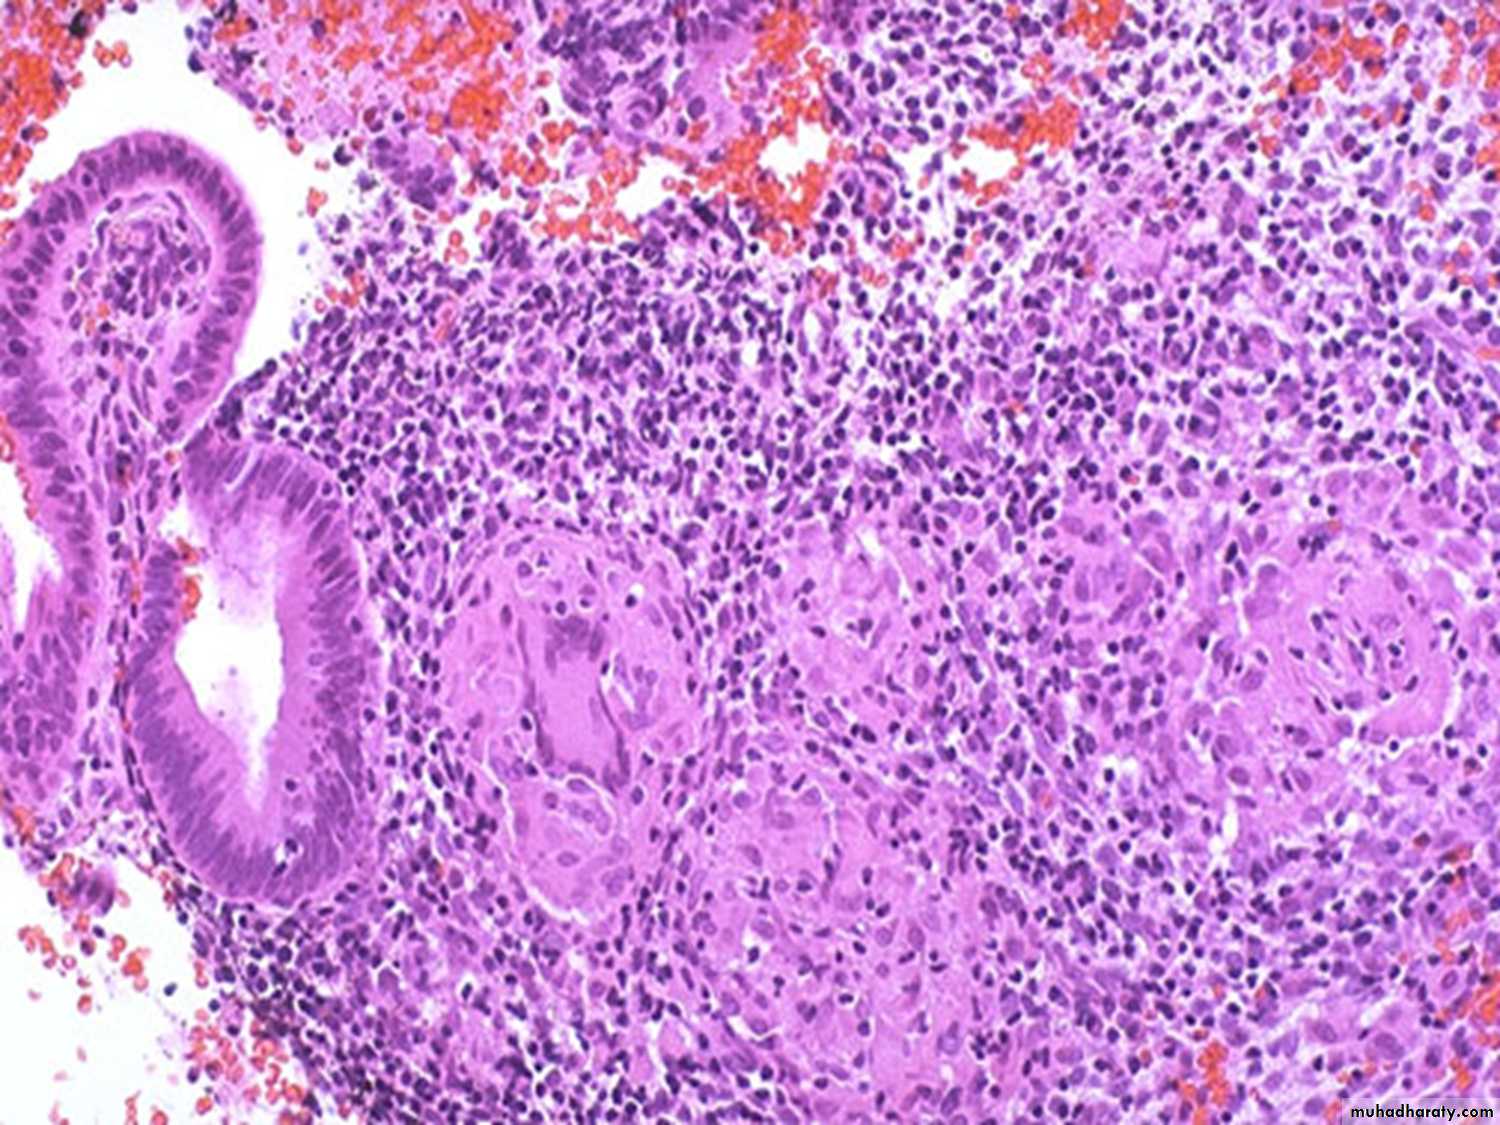

The inflamed endometrium is edematous & congested with polymorphnuclear cells infiltrate not only in stroma but also in the glands where small intra luminal abscesses are commonly seen.

There are scattered neutrophils in glands and stroma, indicative of acute endometritis